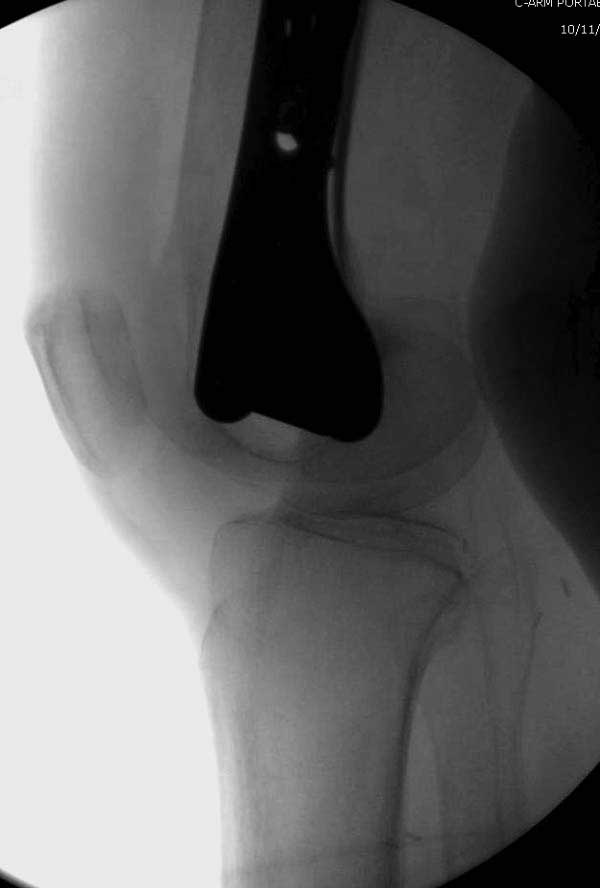

No comment.

End of story.

Третья операция-продолжения усилии “синьорами пэрами” по разрушению нормальной анатомии. Крест на головку! По видимому возраст позволяет биполярную конструкции, и при дефекте calcar пошли на обычный цементный. Ягодичные мышцы потеряли связь с вертелом, т.е. отсутствует верхний удержатель, и результат “a Big Screw Up!” Снимки вызывают головокружение!

Если хирурги не устали от своих “творчеств”, тогда можно ре-оперировать с calcar replacement stem, и собрать остаток ягодичных мышц. Глубина и отстутствие артроза позволяет применить любой, биполярный или тотальный, хотя принять решение можно после ревизии ацетабулума.

Такие “чужие осложнения” встречаются у всех и представляю банальный случай, который шаг за шагом показано как перерос в более сложный процесс... Больная 70 лет, множественные ко-морбидности, чрезвертельный перелом первоначально фиксирован Гамма 3. Осложнение в течение 6 недель, ревизия тотальной артропластикой и во время установки ножки обнаружена трещина диафиза (17), из малого доступа фиксация алло-графтом.

Обычно после чрезвертельных переломов, за исключением молодых, у пожилых остается нестабильность при движении. Часто падают и после 3х мес. в результате падения обнаружен перипротезный перелом (22-23), который зафиксирован Синтез пластиной.

Повторно поступает после двух с половиной лет, где обнаруживается перелом на второй стороне. Немного сложно, но для фиксации выбрали Antegrade InterTan Smith Nephew Nail и с момента фиксации более 3х мес.